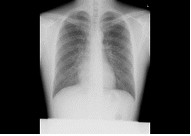

胸部、腹部をはじめ、頭部、椎体(頚椎・胸椎・腰椎)、骨盤、四肢など、全身の骨の撮影を行います。X線を用いて痛みを感じることなく、体の中の様子を調べることができる検査です。病変や骨折などを診断しやすくするため、いろいろな体位、方向から撮影します。 読影(画像診断)は日本放射線学会で認定されている経験豊富な放射線専門医が担当しています。

| 胸部 | 腹部 | 頭 |